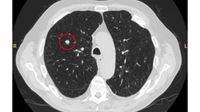

Cortes de tomografia computadorizada (TC) de dois casos com nódulos perifissurais benignos. Observe as margens lisas e a fissura adjacente normal e intacta

Do acervo de Dr. George Tsaknis, MD, PhD, FRCP (Londres), MRQA, MAcadMEd, PGCert; usado com permissão